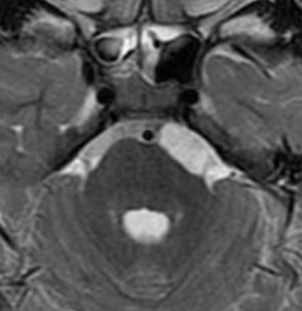

Эпидермоидные кисты (эпидермоиды) - доброкачественные врождённые образования. Они происходят из эктопических эпидермальных клеток и развиваются в период закрытия, в 3-5 нед. эмбриогенеза, как следствие неполного разделения нейрональной и покровной эктодермы. Частота составляет около 1% от внутричерепных образований. Обычно диагностируются в возрасте 25 - 45 лет. Локализация эпидермоидов может быть любой, но типичная - мосто-мозжечковый угол (третье по частоте образование этой области), предмостовая цистерна, параселлярная область, четверохолмие и желудочковая система, очень редко в полушариях, спинном мозге и интрадиплоидно. Растут они интра- или экстрадурально, экспансивно, медленно, сдавливая ствол мозга, внутричерепные нервы, но не разрушая кость. Иногда захватывают сосуды и нервы. По характеру роста их можно отнести к опухолевидным образованиям. Вокруг эпидермоидов нередко развивается асептическое воспаление, а при разрыве содержимое (жир, кератин) прорывается в ликворные пространства. Клинические проявления зависят от локализации и масс-эффекта.

При МРТ головного мозга картина неспецифическая и зависит от содержимого кисты. Если она не содержит жира, то имеет ликворную интенсивность сигнала . В таком случае эпидермоидная киста трудно отличима от арахноидальной, хотя, как правило, не столь однородная. На МРТ типа FLAIR и диффузионно-взвешенных МРТ изображениях содержимое эпидермоидов светлее ликворного. Жировое содержимое, такие эпидермоиды еще называют холестеатомой, приводит к высокому сигналу на Т1-взвешенных МРТ головного мозга. Видимо, он обусловлен липидами, но не холестеролом. На Т2-взвешенных МРТ головного мозга он менее интенсивен чем ликвор. Контуры эпидермоидов всегда четкие. Холестеатомы составляют всего 3-5% от эпидермоидов. В 15-20% случаев встречается кальцификация по переферии кисты. Редко наблюдается контрастирование стенок.

При МРТ головного мозга картина неспецифическая и зависит от содержимого кисты. Если она не содержит жира, топри МРТ головного мозга эпидермоидная киста имеет ликворную интенсивность сигнала. В таком случае эпидермоидная киста трудно отличима от арахноидальной, хотя, как правило, не столь однородная. На FLAIR томограммах и диффузионно-взвешенных МРТ головного мозга содержимое эпидермоидов светлее ликворного. Жировое содержимое, такие эпидермоиды еще называют холестеатомой, приводит к высокому сигналу на Т1-зависимых МРТ головного мозга. Видимо, он обусловлен липидами, но не холестеролом. На Т2-взвешенных МРТ головного мозга он менее интенсивен чем ликвор. Контуры эпидермоидов на МРТ всегда четкие. Холестеатомы составляют всего 3-5% от эпидермоидов. В 15-20% случаев встречается кальцификация по переферии кисты. Редко наблюдается усиление стенок кисты при МРТ головного мозга с контрастированием.